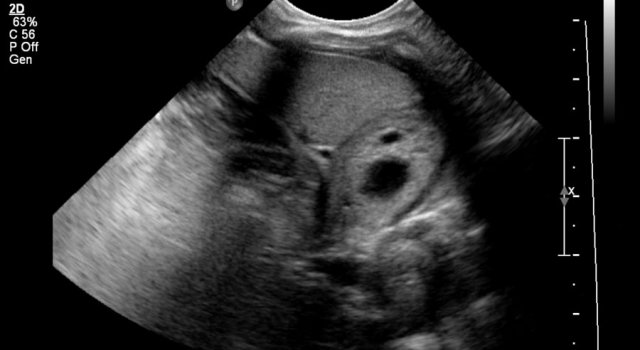

Here an ultrasound image of a five-month-old boy with an antenatally detected dilated pyelocalyceal system and no visible ureter, in accordance with a ureteropelvic junction stenosis.

On a sagittal image the dilated pyelocalyceal system is well seen.